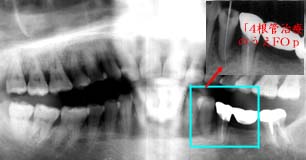

折角「4を残したのに…何で抜いた!!?

初診時 パノラマ 9年後 パノラマ

中程度以上の歯槽骨吸収を認める

47歳 女性

更に進行したとはいえ、何で抜いた?

主訴は、「4部の腫脹。

初診時口腔内およびX線所見:

カリエスが少なく歯の保存状態は良好ではあったが、清掃状態はやや不良で全体に中程度の 歯槽骨吸収が認められ、歯周疾患傾向が強そうな状態であった。 「4に上行性歯髄炎と思われる骨吸収像が、辺縁部と根尖部に認められた。

処置および経過:

「34根管治療の上、「345 Fop+HAP 施行。「34を連結固定後メインテナンスに移行したが、 そのまま来院が途絶えて9年を経過した。

4|が自然脱落した」と訴えて来院された患者さんのレントゲン写真をみて、愕然とした 怒りにも近い気持ちが交錯した。歯槽骨の吸収が全体に進行して、動揺が認められるように なったのは当時の進行傾向から当然のことである。歯周疾患の進行により抜歯された右下 の大臼歯もさることながら、九死に一生を得た「4を尻目に、比較的健全と思われた「57の 喪失には言葉もない。

「他の歯医者に抜かれてしまいました。何とかして下さい。」と今更いわれても…。 幸いにも、8|が比較的健全な状態であったので、「6部に自家移植をして 「BC5E Bridge装着にて一件落着。